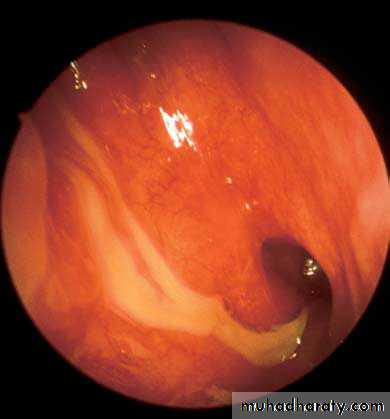

Another diagnostic modality for sinusitis is nasal endoscopyView into left nasal cavity demonstrates a polyp (P) extending from the middle meatus.

p